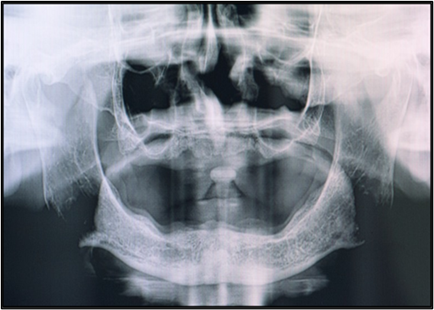

Figure 5: Pre-Treatment OPG.

A 58-year-old female, presented with complaint of constant dislodgement of her denture during chewing, accompanied by significant difficulty in chewing food over the past eight months. Her dental history showed a gradual loss of teeth spanning approximately seven years, with complete edentulism established six years ago. A pre-treatment panoramic radiograph revealed generalized alveolar bone resorption, more pronounced in the mandibular ridge. The maxillary alveolar ridge exhibited moderate resorption, with diminished bone height particularly in the anterior region corresponding to the flabby premaxillary tissue. A conservative, non-surgical prosthodontic rehabilitation was planned.